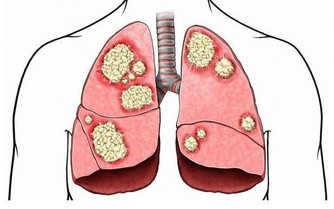

腫瘤阻塞,當腫瘤長至相當體積,或浸潤腸壁肌層時,

可引起腸管狹窄,腸腔變小,腸內容通過受阻。

當大腸腫瘤相對較大且有糜爛、潰瘍或感染時,

才可能發生大便習慣、次數的改變,以及便秘或不明原因的腹瀉。

如果癌腫突出向直腸腔內生長,導致腸腔相對狹窄,

則排出的大便往往變細、變形,可呈扁形,有時變形的大便上附著一些血絲。